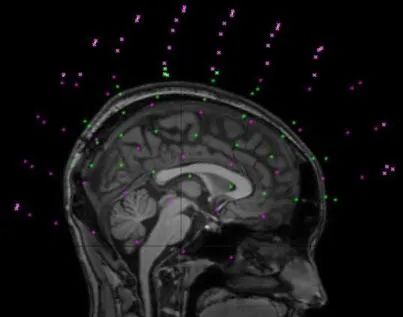

MEG-MRI多模态配准

以基于特征的图像配准通用流程为例:

基于特征的图像配准通用流程

1.Feature detection: 特征检测

特征检测是图像配准过程的一项重要任务。根据问题的复杂性,通常分为手动或自动检测,但通常优先选择自动特征检测。

封闭边界,边缘,轮廓,线交点,角点,以及它们的代表点如重心或线末端(统称为控制点)可以作为特征。由特殊对象组成的这些特征必须易于检测,即特征将是物理上可解释和可识别的。

参考图像必须与浮动图像共享足够多的共同特征集合,而不受到任何未知遮挡或意外改变的影响。用于检测的算法应该足够稳健,以便能够在场景的所有投影中检测相同的特征而不受任何特定图像变形或退化的影响。